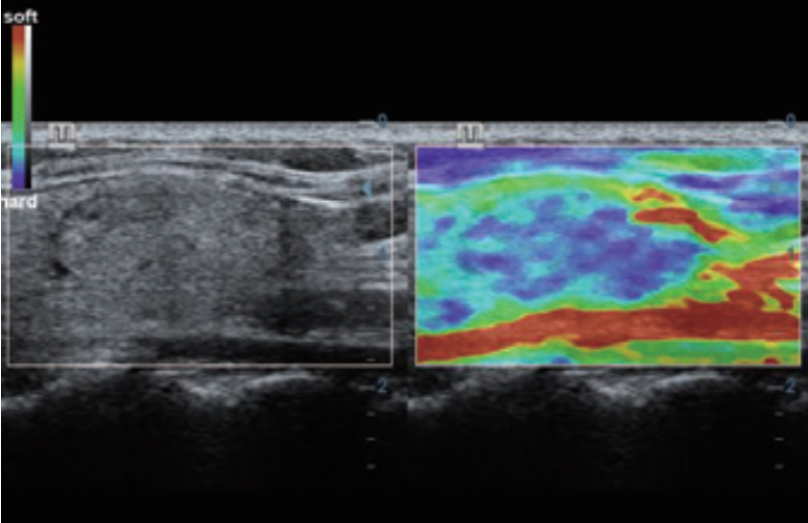

- Posee variadas herramientas que le permite al médico especialista realizar estudios de mejor calidad, como; iClear reducción de moteado, PSH imágenes por armónicos, iBeam formación de imágenes espaciales compuestas.

- La tecnología en transductores ComboWave utilizan un nuevo tipo de material piezoeléctrico compuesto que optimiza notablemente el espectro acústico y reduce la impedancia acústica.